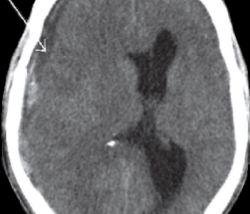

Burr hole drainage is a standard treatment for chronic subdural hematoma, but what if the patient then complains of frequent and/or really bad headaches, or even nasty neck pain?

Postoperative headaches, then, are to be expected, following burr hole drainage of a chronic subdural hematoma.

But beware if the headaches start becoming worse and more frequent.

This could signal a recurrence of the chronic subdural hematoma (there is a 15 percent recurrence rate).

This happened to my mother; she had a recurrence, and at some point on the headache continuum, the cause of the headaches transformed from postoperative and incisional, to a recurrence of the chronic subdural hematoma.

Ten days after the burr hole drainage, the headache pain was so unbearable that she couldn’t sleep through the night.

A few other new symptoms were present, convincing me she had a recurrence of the chronic subdural hematoma (or, to put it another way, perhaps the burr hole draining wasn’t complete, and residual fluid and leaking continued to build up).